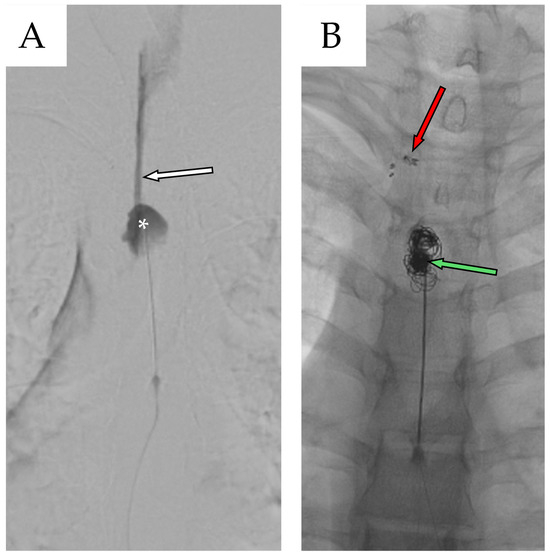

A new multidisciplinary consultation was convened to address the need for definitive surgical repair. Two months after second admission, the patient underwent a third and final surgical procedure, consisting of bilateral T4 laminectomy with clipping of the T3 fistulous tract combined with percutaneous repair of the dural leak using metallic coils placed within the cystic cavity followed by a new blood patch (Figure 8).

Figure 8. (A) Preoperative fluoroscopic myelography after contrast agent infusion shows the caudal portion of the cyst (white asterisk), along with the fistulous stream originating from the overlying fistulous tract (white arrow with black outline). (B) Postoperative fluoroscopic myelography confirms closure of the fistula at the T3–T4 level using metal clips (red arrow with black outline), while the remaining subarachnoid cavity (SAC) is filled with metallic coils and blood (green arrow with black outline).